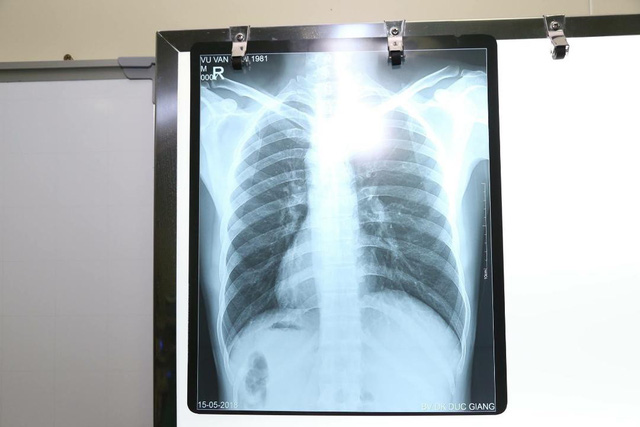

19/12/2018 16:01Nam bệnh nhân phủ tạng đảo ngược ở Hà Nội: tim bên phải, gan bên trái

Nam bệnh nhân 37 tuổi ở Gia Lâm, Hà Nội vào Bệnh viện Đa khoa Đức Giang với các dấu hiệu rõ rệt của chứng đau ruột thừa, tuy nhiên điều làm các bác sĩ ngạc nhiên là thông thường đau ruột thừa sẽ đau ở hố chậu phải, nhưng bệnh nhân này lại đau ở bên trái.

Ngay khi có kết quả siêu âm, các bác sĩ rất bất ngờ khi thấy trái tim và dạ dày của bệnh nhân nằm bên phải, còn gan và ruột thừa lại nằm bên trái, trái ngược hoàn toàn so với bình thường.

Sau khi siêu âm và thăm khám xác định, các bác sĩ đã tiến hành phẫu thuật nội soi cắt ruột thừa cho bệnh nhân an toàn. Hiện sức khỏe bệnh nhân đã bình phục. Bệnh nhân cho biết trước đây bệnh nhân đã đi khám và biết trái tim và các tạng của mình nằm ở vị trí đối lập so với thông thường, nhưng mọi sinh hoạt của anh vẫn như bình thường. Anh đã lập gia đình và có con.

Bác sĩ Nguyễn Sơn Hà, trưởng khoa ngoại tổng hợp Bệnh viện Đa khoa Đức Giang, cho hay thông thường những trường hợp đảo lộn phủ tạng có kèm theo dị tật về chức phận của các hệ cơ quan, như dị tật về van tim, dị tật về đường ra của các động mạch, tĩnh mạch lớn của tim. Phẫu thuật trên các bệnh nhân như thế này là thay đổi hoàn toàn về giải phẫu và có thể có nguy cơ trong phẫu thuật hoặc sau phẫu thuật.

Bác sĩ Hà cũng cho hay đây là một dạng dị tật có tính di truyền lặn tương đối hiếm gặp, tỉ lệ khoảng 1/10.000 người. Khoảng 5-10% trong số này có dị tật tim bẩm sinh, còn lại có cuộc sống bình thường.